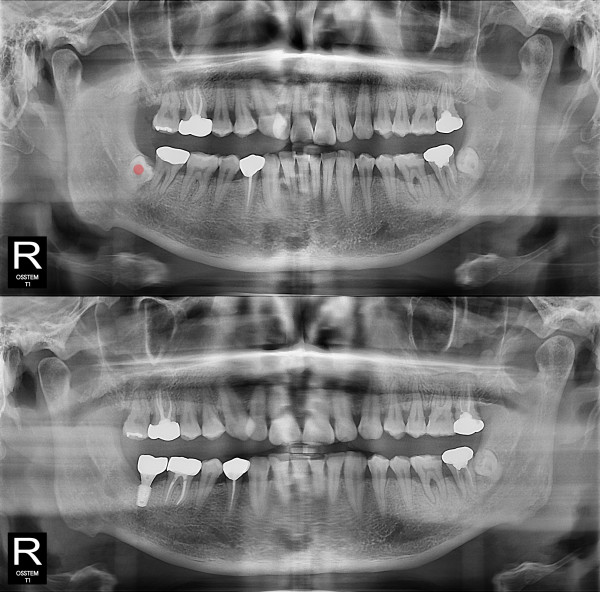

智齿拔除 完全埋伏智齿

b047bd763797d0ee5fe0c71c12970e9f_1766119706_3898.jpg